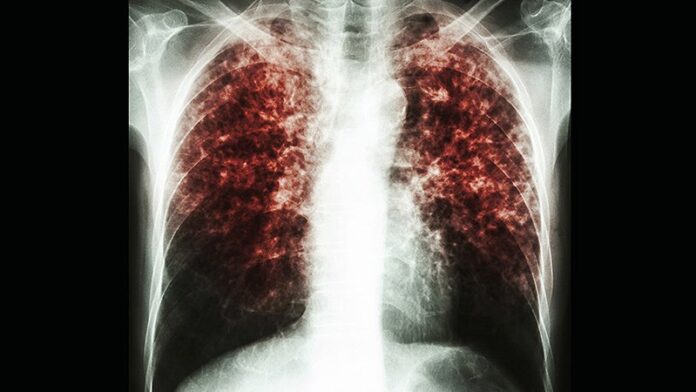

Chest X-rays are frequently used to identify possible active tuberculosis infections. If the scan shows abnormalities in the lungs, the patient may have damage due to a TB infection. To confirm the infection, health practitioners take a sputum sample – phlegm that the patient coughs up – and analyze it for tuberculosis bacteria. Then, further diagnostic tests reveal if the bacteria is resistant to drugs. Villa-Castillo has seen long delays in the arrival of these diagnostic tests due to the pandemic and explains that the testing equipment is critical, “because then you can quickly start the type of treatment specific to the strength of the bacteria.”